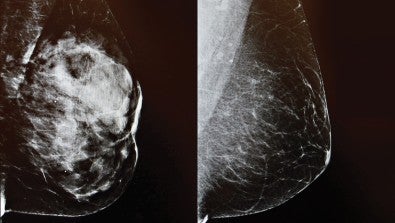

What It Means If You Have Dense Breast Tissue

November 19, 2024

Image

3D imaging Mammogram at LVHN